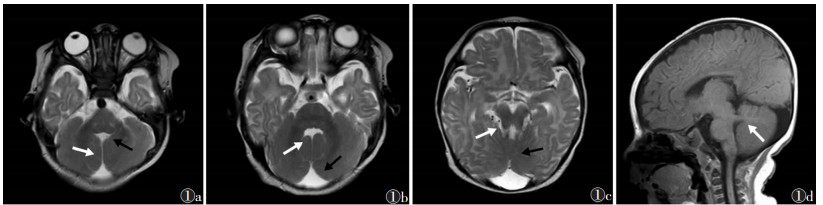

2 结果4例的MRI及CT特征:①小脑半球“中线裂”,小脑蚓部完全或部分缺损致两侧小脑半球紧密靠近而不相连,脑脊液进入其中并与前方第四脑室相连(图 1a,1b,2a),其中2例小脑蚓部完全缺损,2例小脑下蚓部缺损;②“臼齿征”,中脑脚间池凹陷增深,中脑峡部(中脑与桥脑连接部)变细,形成“臼齿”的“牙冠”,小脑上脚增厚、延长,并水平走行(图 1d),与第四脑室顶部形成“臼齿”的“牙根”(图 1c,2b~2d);③“蝙蝠翼状”、“三角形”第四脑室,中脑和桥脑连接部第四脑室呈“蝙蝠翼状”改变(图 1b),第四脑室中部呈“三角形”改变(图 1a)。1例合并枕大池扩大(图 1b)及幕上后纵裂永存镰状窦,1例脑白质髓鞘化发育落后于同龄,1例额颞部蛛网膜下腔增宽。

| 图 1 男,90 d,以发育迟缓,四肢肌张力偏低,双眼运动障碍3个月就诊 图 1a 轴位T2WI示两侧小脑半球之间“中线裂”(白箭)、“三角形”第四脑室(黑箭) 图 1b 轴位T2WI示“蝙蝠翼状”第四脑室(白箭),枕大池扩大(黑箭) 图 1c 轴位T2WI示中脑水平“臼齿征”(白箭),小脑上蚓部可见(黑箭) 图 1d 矢状位T1WI示小脑上脚增粗,水平走行(白箭) |